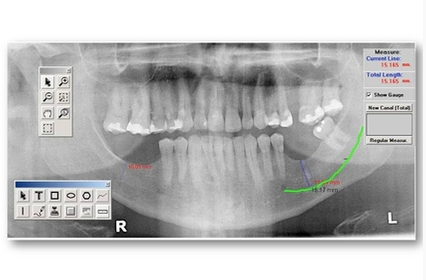

Nous utilisons un appareil d’imagerie 3D, le Carestream 9300 Select de haute technologie, afin de prendre des radiographies en 3D.  La radiographie en 3D est particulièrement utile en implantologie dentaire pour recueillir des images précises sur l’architecture osseuse et les structures anatomiques importantes, ce qui permet un diagnostic approfondi et ainsi établir un plan de traitement sécuritaire pour les patients.

La tomographie volumique à faisceau conique (TVFC), génère un ensemble de données 3D à des doses de radiations beaucoup plus faibles que leurs homologues CT scan médicaux, soit des doses allant jusqu’à 10 fois moins élevées.  En effet,  la  tomographie volumique à faisceau conique (TVFC) représente la dernière génération d’appareils d’imagerie médicale. Lors d’un scan TVFC, le scanneur tourne autour de la tête du patient, pour obtenir jusqu’à près de 600 images distinctes. Le logiciel de numérisation recueille et transforme les données en données anatomiques de trois dimensions qui peuvent ensuite être manipulées et visualisées avec l’aide d’un logiciel spécialisé. Nous utilisons ces images de haute précision pour planifier les cas et pour la chirurgie guidée par ordinateur, rendant ainsi les traitements plus confortables pour les patients.

L’imagerie 3D est utilisée dans les diverses spécialités dentaires telles que, la chirurgie maxillo-faciale, l’implantologie, l’orthodontie, l’endodontie, la parodontie, ainsi que pour le dépistage de pathologies buccales.

Implantologie: de meilleures images sur le statut osseux ; l’emplacement du nerf mandibulaire, la santé des sinus, etc.

Endodontie: Visualisation des canaux en 3D et l’état des dents.